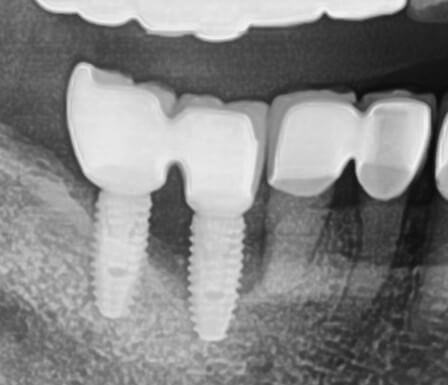

국내 임플란트 장점?

디오 임플란트

최대 2배까지 수명 유지가 가능한 디오 임플란트는 임플란트 또는 뼈 부착에 좋은 티타늄 표면을 이용하여 임플란트 수명이 일반 임플란트 보다 수명이 깁니다.

네오 임플란트

임플란트와 잇몸 사이가 좁아 즉, 벌어지는 틈이 별로 없어서 각종 세균의 번식을 억제할 수 있습니다.

오스템 임플란트

임플란트와 치아 뼈 사이의 닿는 면적이 넓어서 치아에 부착되는 시간이 짧으므로 통증 시간이 짧습니다.

덴튬 임플란트

많은 치과 의사들이 꾸준하고 오랜 임상 자료를 토대로 한 치과 의사들이 추천하는 임플란트이며 가격은 평균 80만 원대입니다.